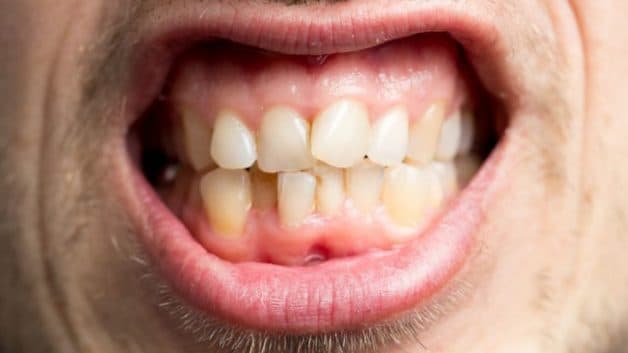

– Răng mọc không đồng đều.

Răng mọc không đều là nguyên nhân gây nên bạch sản niêm mạc miệng